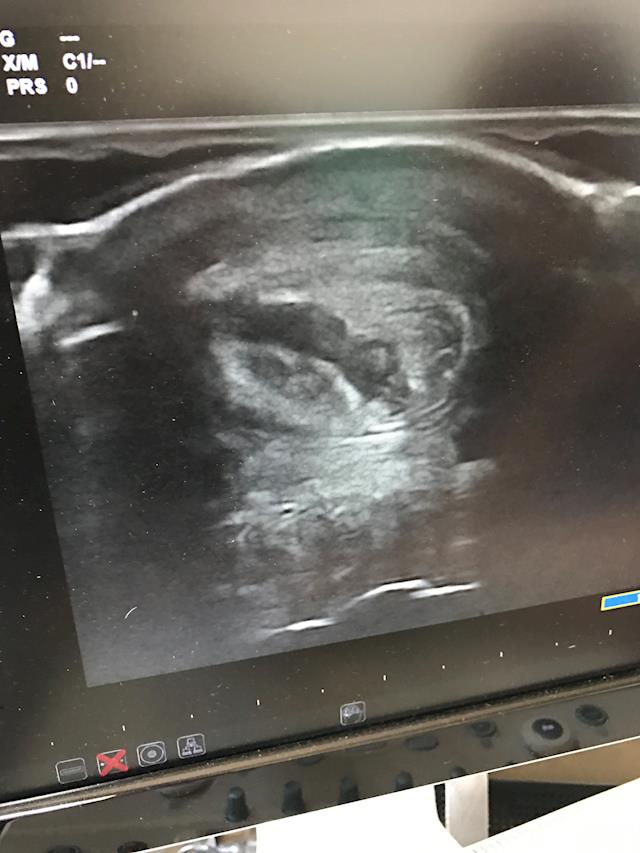

Main image

Here are some snaps from our vet visit